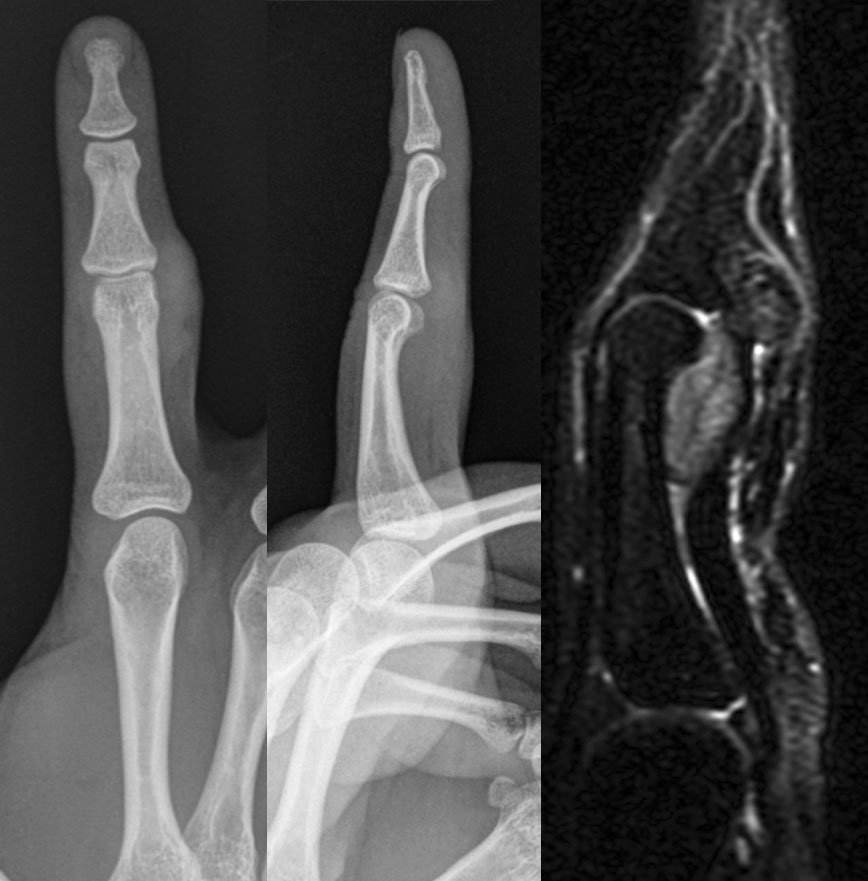

Mujer de 24 años, sin antecedentes de interés, que presenta tumoración en el 2º dedo de la mano derecha. Nota crecimiento progresivo.

No dolorosa, aunque limita algo la movilidad activa. La movilidad pasiva es completa.

Se solicitan pruebas de imagen: RX, ECO, RM.

1. ¿Como describirías los hallazgos en RX y ecografía?

- A. Tumoración de partes blandas que asocia erosión ósea adyacente.

- B. Tumoración de partes blandas sin erosión ósea adyacente.

- C. Derrame articular.

- D. Erosiones articulares con componente de partes blandas asociado.

- E. Ninguna de las respuestas es correcta.